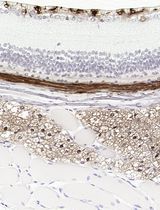

采用 Davidson 固定液和黑色素漂白法优化小鼠眼组织切片的免疫组化染色

Anne Nathalie Longakit [...] Catherine D. Van Raamsdonk